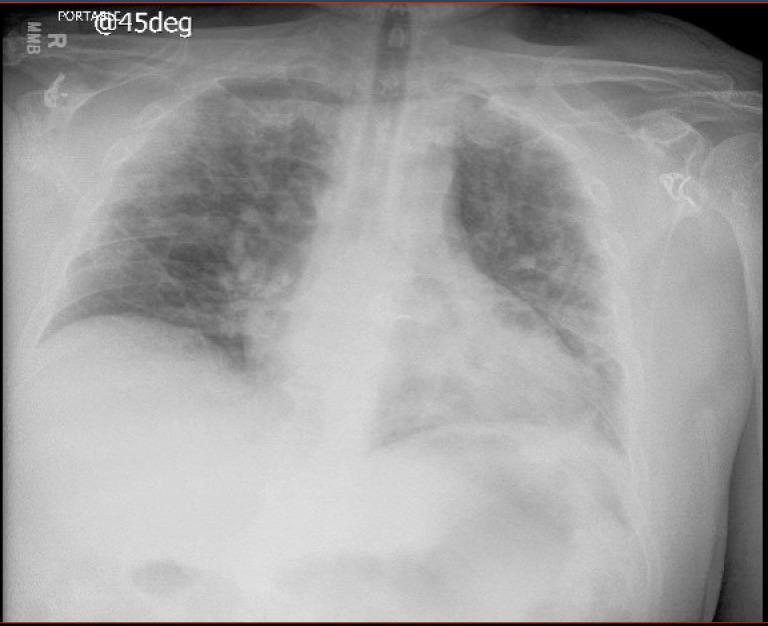

Acromegaly is a rare disorder of unregulated hypersecretion of growth hormone that causes cardiovascular, metabolic and respiratory complications. Herein, we describe the case of a middle-aged man admitted to the hospital with severe COVID-19 found to have clinical and biochemical evidence of acromegaly. His respiratory status declined despite initiation of standard treatments, prompting initiation of subcutaneous octreotide. Following initiation of this therapy, he rapidly improved and was discharged from the hospital 2 days later. Subsequent workup revealed a pituitary macroadenoma that was surgically removed, with improvement in his acromegaly symptoms. COVID-19 disease severity is increased by pre-existing diabetes, lung disease and immunosuppression. Although this patient had obstructive sleep apnoea and pre-diabetes, we hypothesise that our patient's acromegaly contributed to his severe course, as reflected by his rapid improvement after starting treatment with subcutaneous octreotide. Acromegaly may predispose to more severe outcomes in patients with COVID-19.

肢端肥大症是一种罕见的生长激素过度分泌的疾病,会导致心血管、代谢和呼吸系统并发症。本文描述了一名中年男性因严重 COVID-19 住院,临床和生化证据显示存在肢端肥大症。尽管开始了标准治疗,但他的呼吸状况仍在恶化,随后开始皮下注射奥曲肽。开始这种治疗后,他迅速改善,两天后出院。进一步检查显示存在垂体大腺瘤,已通过手术切除,肢端肥大症症状得到改善。COVID-19 疾病的严重程度会因糖尿病、肺部疾病和免疫抑制等先前存在的疾病而增加。尽管该患者患有阻塞性睡眠呼吸暂停和糖尿病前期,但我们假设他的肢端肥大症导致了他的严重病情,因为他开始皮下注射奥曲肽后病情迅速改善。肢端肥大症可能使 COVID-19 患者的病情更严重。